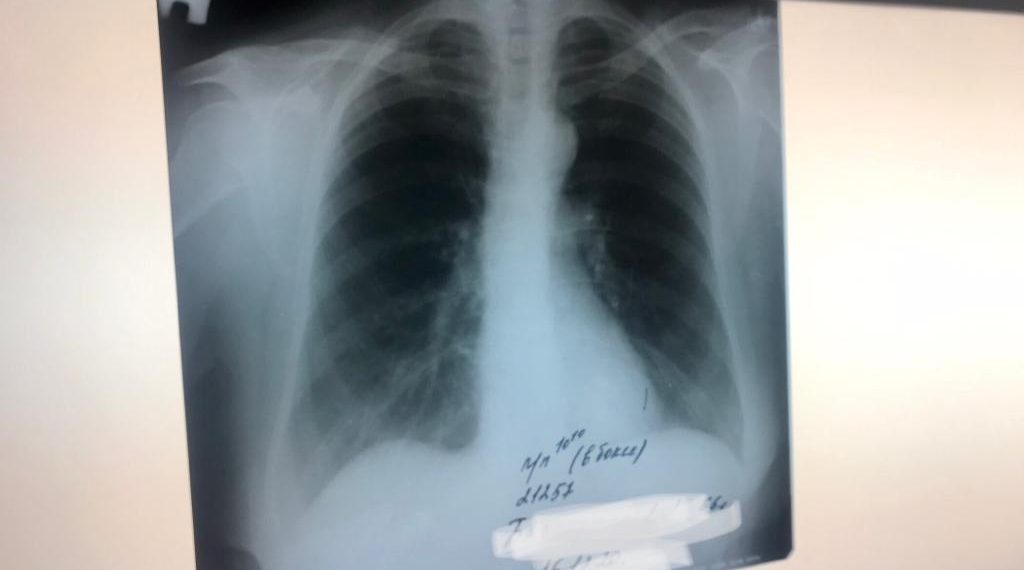

В регионе отмечается устойчивая тенденция по улучшению ситуации с туберкулезом. Показатель заболеваемости этой инфекцией уменьшается ежегодно на протяжении 10 лет, в 2022 году заболеваемость по территории Новосибирской области снизилась на 6,3%. В тоже время показатели заболеваемости еще не достигли среднероссийских, что требует дальнейшей активизации работы.

В предшествующий период в Новосибирской области создана единая система оказания специализированной медицинской помощи по профилю «фтизиатрия». Объединение областной туберкулезной больницы и противотуберкулезного диспансера позволило обеспечить полную преемственность стационарного и амбулаторного этапов лечения. Создана новая система лекарственного менеджмента, позволяющая упростить лекарственное обеспечение пациентов на всех этапах лечения. Оптимизирована маршрутизация для больных, нуждающихся как в амбулаторной, так и в стационарной помощи. Реализуется пилотный проект по внедрению модели оказания противотуберкулезной помощи на основе пациент-ориентированного подхода. В прошлом году приступил к работе новый диагностический корпус детской туберкулезной больницы.